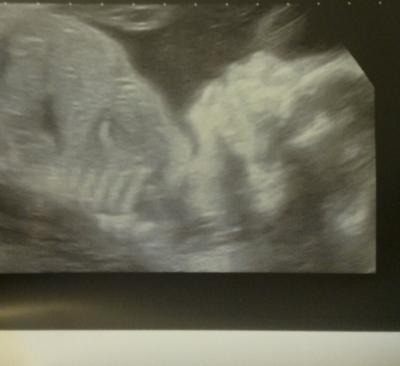

Hallo liebe Muttis :) Hoffe euch geht es soweit gut!? Wir hatten heute endlich wieder unseren Termin beim FA. War natürlich supi Dem Baby geht's gut alles ist so wie es sein sollte. Hat sich immer noch nicht SEHR GUT zwischen die Beine schauen lassen somit denkt er weiterhin ein Mädel. :) Zuckertest gut etwas wenig aber gut. Wegen den Rippen ist halt so das es weh tut. Wenn ich mag soll ich zum Ultraschall obs Gallensteine sein könnten wovon er nicht ausgeht. Schönen Tag euch noch Glg Sabrina :)

Bild zu nach 5 Wochen :) - Forum für Mai - Mamis

freut mich das alles supi ist. Schönes Bildchen haste da bekommen.

Super, dass alles so toll läuft! Wirklich süsses Bildchen!!